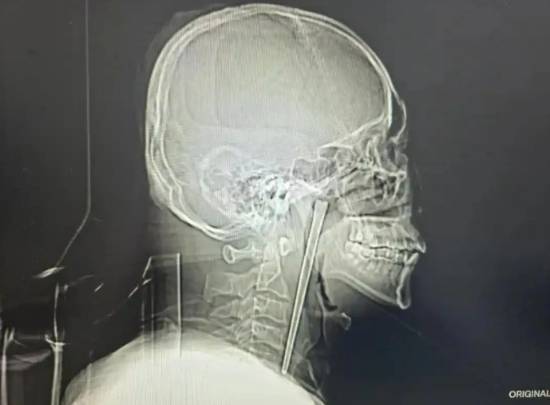

辽宁大连46岁的王先生因咽部突发剧烈疼痛、异物感难忍,前往大连理工大学附属中心医院耳鼻咽喉头颈外科就诊,一项检查结果让医护人员大吃一惊——一根长达12厘米的金属筷子,竟在他的咽部“潜伏”了整整8年之久。有网友留言感叹“真是个狠人,竟然能忍8年”。

接诊的黄巍鹏医生详细询问病史后,立即为王先生安排电子喉镜检查,结果清晰显示,其右侧咽后壁黏膜下、软腭后侧有一根金属筷子嵌入,肉眼可见部分约3厘米。万幸的是,经细致探查,异物邻近的咽部黏膜未出现明显破溃、出血及化脓情况,声带活动正常,喉腔结构也未受到压迫移位,为后续手术创造了良好条件。